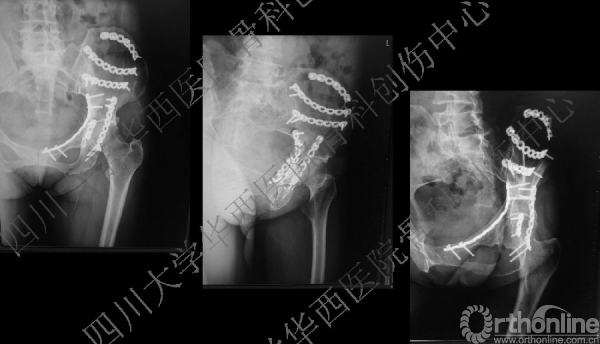

术后X线片

这是术后的X线片,患侧正位、髂骨斜位、闭孔斜位。

术后三维重建后面观,发现后壁的骨折有明显的移位,后脱位的风险增加,我们决定!

3天后

3天后,行后路切开复位内固定术。